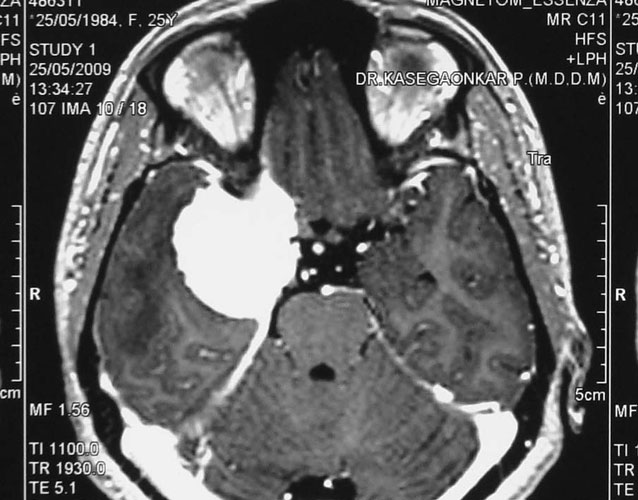

Medulloblastomas

Medulloblastomas are common tumors in childhood, often presenting with vomiting and headache. These tumors are located in midline of the cerebellum (back of the head). Diagnosis is made with MRI, and complete excision can be done safely in majority of the children.